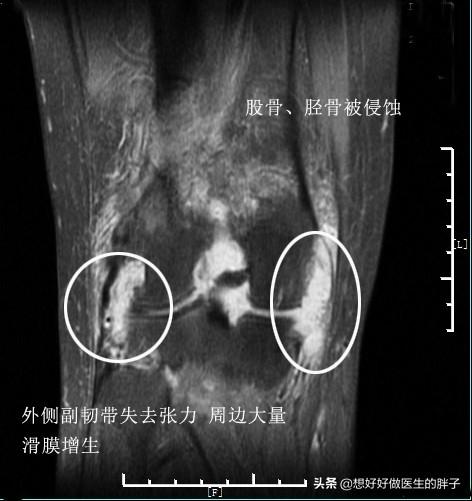

看起来这些病态的滑膜就像是魔鬼的触角一样恐怖,事实也是如此,尤其是对于类风湿关节炎以及痛风性关节炎的患者,这些滑膜会在关节内长久的存在,不断侵蚀关节的软骨以及骨骼。下图就是一例严重类风湿关节炎患者的核磁片子,他的关节软骨以及骨骼看起来已经像是被老鼠啃噬过一样了,这都归咎于类风湿滑膜炎的侵犯!

类风湿关节炎的病理基础就是关节腔滑膜的炎症,病理表现主要有滑膜衬里细胞增生、间质大量炎性细胞浸润,以及微血管的新生、血管翳的形成及软骨和骨组织的破坏等。

在类风湿关节炎的急性期会有大量的关节渗出,热敷会导致患者疼痛明显的加重。所以在类风湿急性期的患者建议您和痛风的患者一样,一定要在医生的指导下进行治疗类风湿关节炎同时采取冷敷的办法,帮助您尽量控制关节腔内滑膜的渗出、减轻滑膜的肿胀、控制滑膜的炎症。

类风湿患者如果常年受到关节积液的困扰,是可以进行关节镜手术清理的,类风湿滑膜炎也是关节镜手术的适应症。建议类风湿患者如果经过系统的保守治疗,仍然深受病痛的折磨,完全可以选择关节镜手术的办法来治疗关节滑膜的炎症。